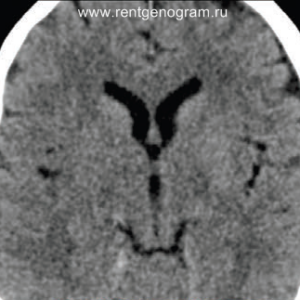

Ранние признаки ишемического инфаркта на КТ:

- уменьшение дифференциации серого и белого вещества;

- фокальная гипоплотность (включая островки, подкорковые ядра и кору);

- утолщение коры и сужение борозд;

- сглаживание контуров извилин и борозд;

- повышенная плотность в артерии (может быть выявлен гиперденсный тромб, обычно в СМА или ВСА);

- незначительная асимметрия мозговых структур в базальных ядрах;

- через 4-5 часов могут появиться признаки уменьшения плотности поврежденных структур мозга.

Острая фаза (6 — 24 часа)

В течение острого этапа на МРТ и КТ выявляются все морфологические признаки ишемического инсульта. Область острого ишемического инфаркта визуализируется как зона ↑Т2, ↑Flair, ↑DWI и ↓Т1 ↓ADC. Можно обнаружить тромб в артерии. На КТ в остром этапе также чётко дифференцируется поражённая область, представляющая собой участок с потерей дифференциации мозговых структур и снижением их плотности. Контрастирование в остром периоде не показывает патологических участков с накоплением контраста.